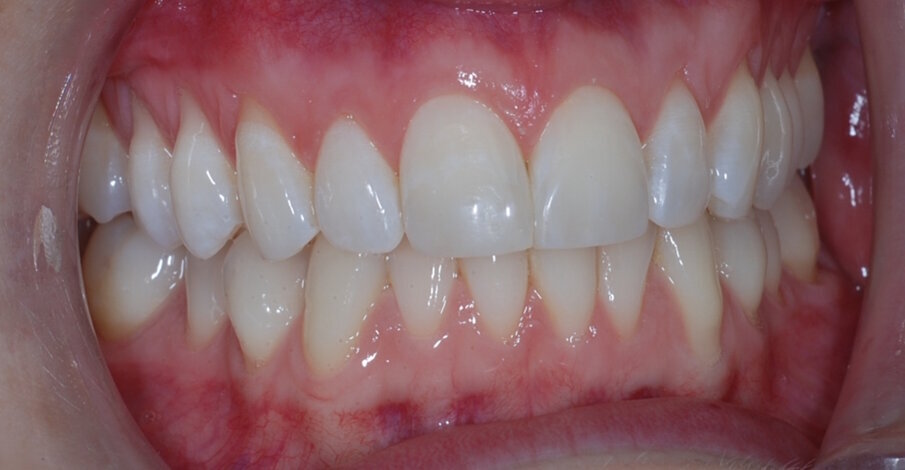

Fig. 16: Post treatment right lateral

Fig. 17: Post treatment left lateral

The patient was very satisfied with the results, especially the fact I was able to improve her smile without affecting the integrity of the enamel. I sent before and after images to the patient at the end of her treatment pathway so that she could see the difference, and she was amazed at how much the aesthetics of her teeth had changed. I was also very happy with the outcome – with the help of the IAS Academy and digital planning tools, treatment was safe and predictable.